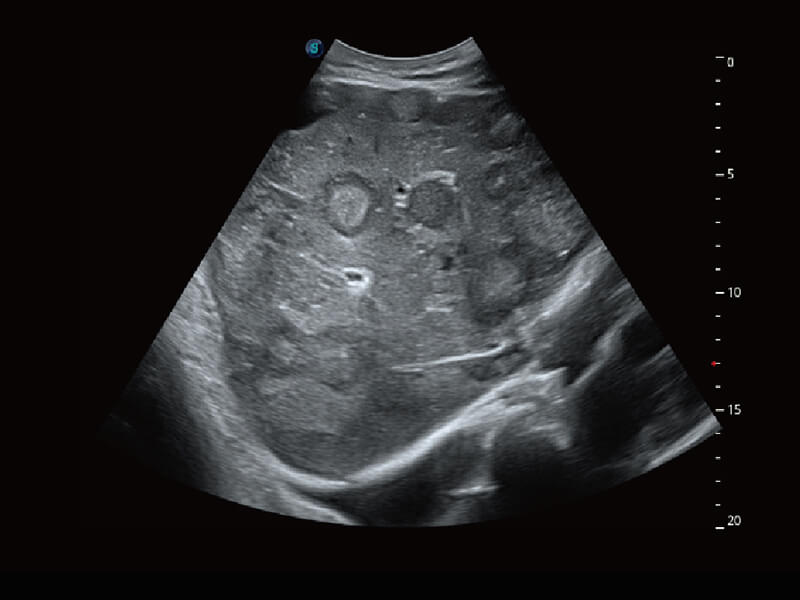

性能优异的硬件架构,极大提升超声系统的运行效率和数据处理能力。相比以往超声成像系统,Wis+平台为您带来极快的响应速度和成像帧频,提升检查流畅度。

S60探头工艺,从前端信号处理每一个环节采集无损声学数据,真实还原组织原貌,再现解剖细节。

超宽频带技术,为容积成像带来优质的二维图像基础,为您呈现丰富的结构细节,栩栩如生地展示宝宝的宫内形态以及各种组织的立体结构。